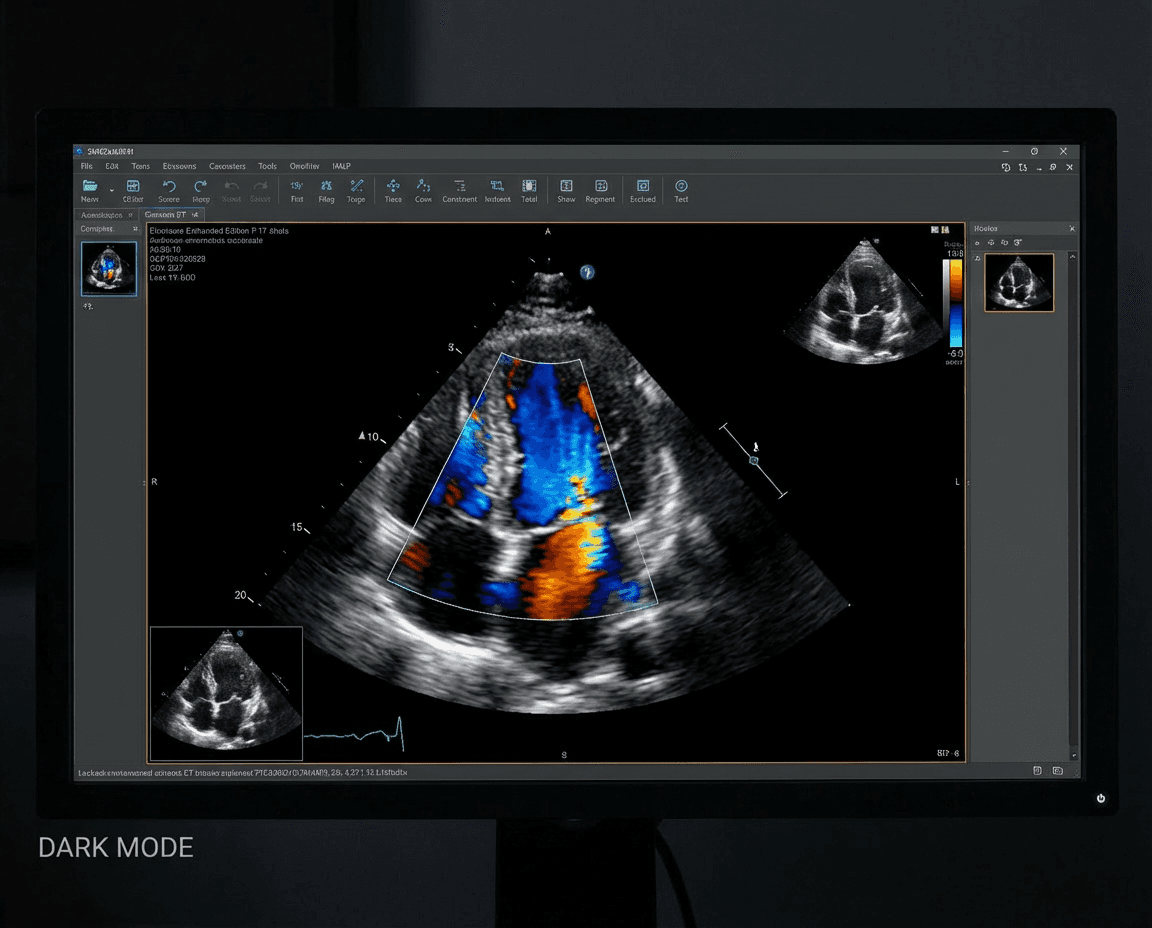

Echo-Heart

Echo-Heart (Echocardiography) is a non-invasive ultrasound imaging technique that provides detailed visualization of the heart's structure and function. Our echocardiography services include transthoracic, transesophageal, and stress echocardiography to assess heart valves, chambers, and blood flow.

Our expert sonographers and cardiologists use state-of-the-art ultrasound technology to diagnose heart conditions, monitor treatment effectiveness, and guide interventional procedures with precision and accuracy.